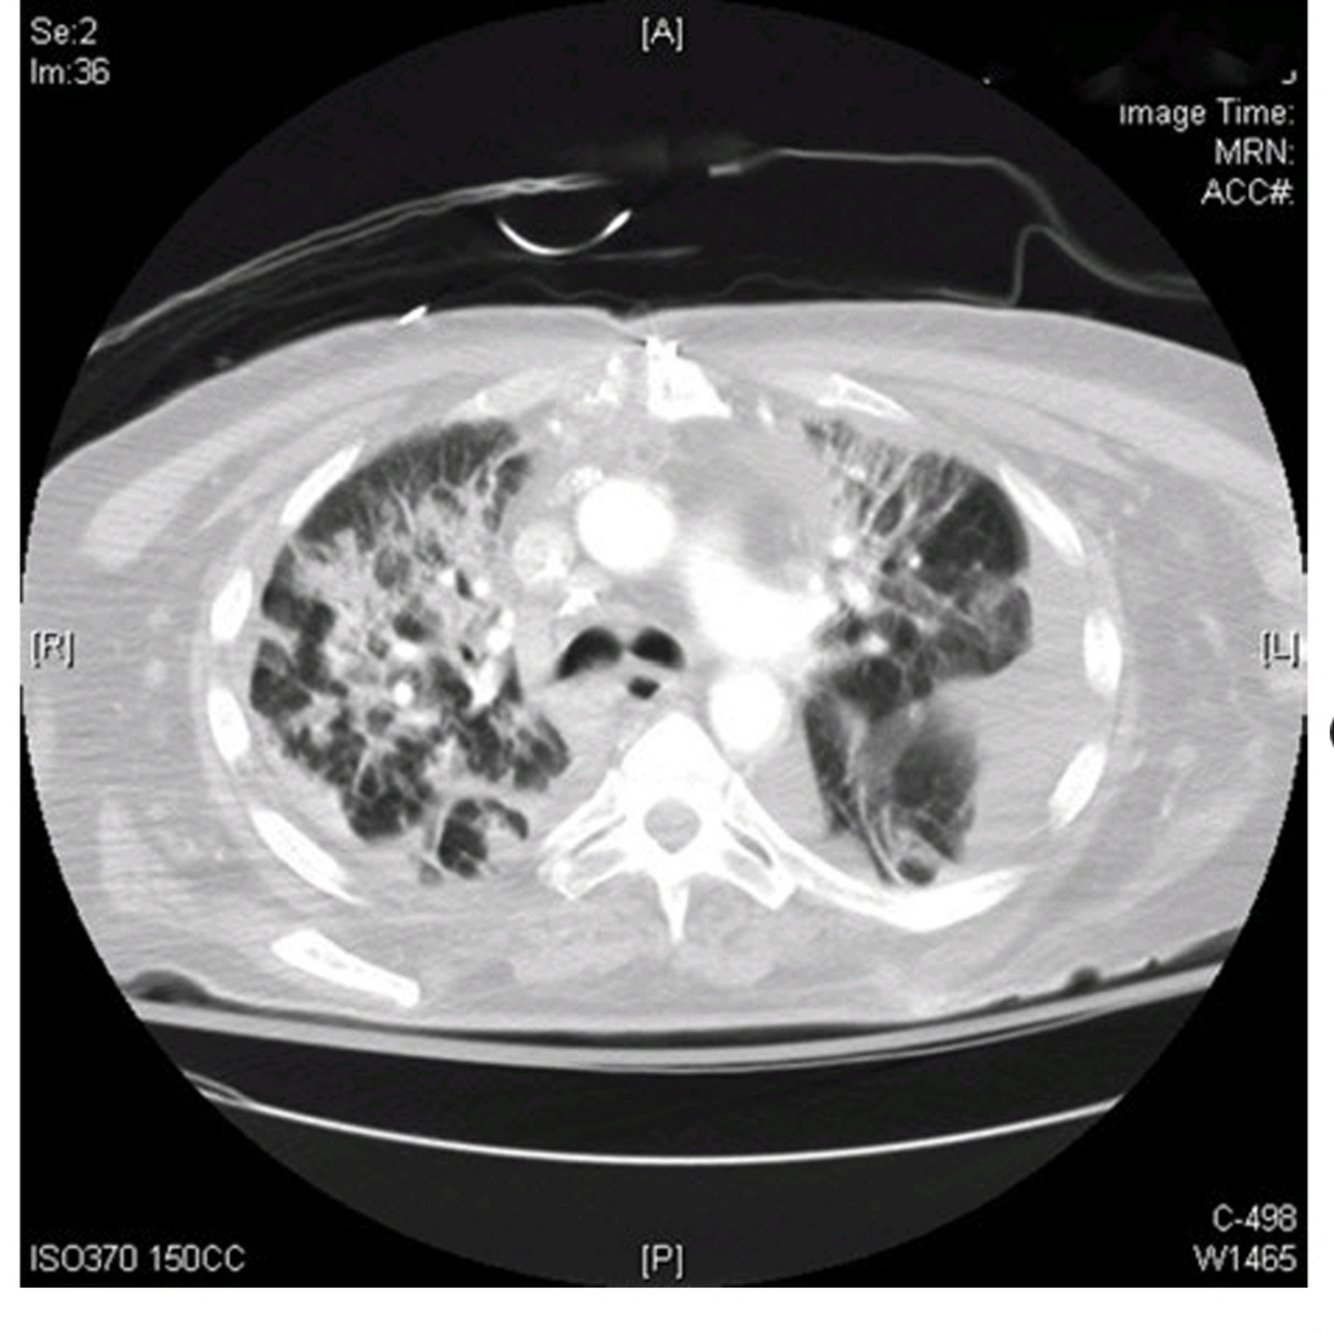

What do the images above show and what is the differential diagnosis based on the appearance seen in the images above?

○ The chest X-ray (Fig. 47.1) shows diffuse bilateral coalescent opacities, whereas the CT chest (Fig. 47.2) shows ground-glass opacification, reflecting an overall reduction in the air content of the affected lung. It is also possible to visualize bronchial dilatation within areas of ground-glass opacification.

Differential diagnosis include

(a) ARDS,

(b) congestive heart failure,

(c) pulmonary hemorrhage,

(d) pneumonia,(

e) transfusion-related acute lung injury, and

(f) non-cardiogenic pulmonary edema.

○ The Berlin definition, dated 2012, states that acute respiratory distress syndrome is an entity characterized by hypoxemia and stiff lungs that occurs within a week of a known clinical insult or new/worsening respiratory symptoms.

° It presents with bilateral opacities on the chest X-ray involving at least three quadrants that are not fully explained by effusions, atelectasis, or nodules.

° Chest computed tomography (CT) findings are opacification that is denser in the most dependent regions as compared to more normal and hyper-expanded lung in the nondependent ones. In addition, CT chest shows widespread ground-glass attenuation, which is a nonspecific sign that reflects an overall reduction in the air content of the affected lung.